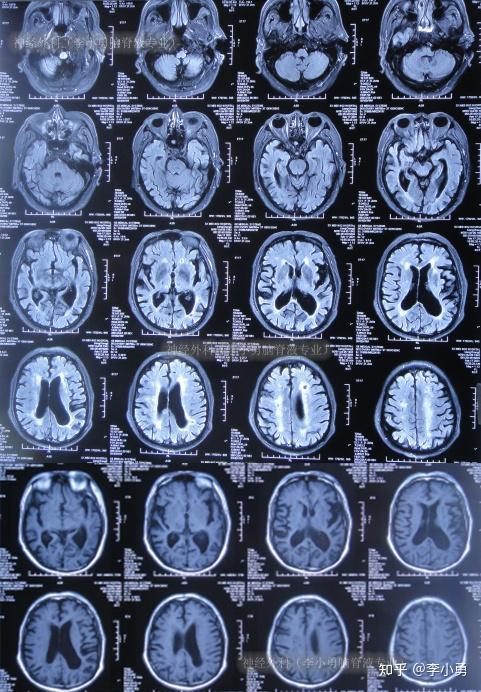

老年正常压力性脑积水:痴呆,日常生活不能自理,走路特别缓慢且小碎步